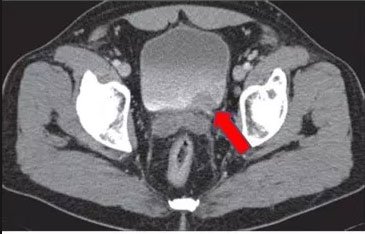

Mesane tümörü tanısı hastanın anamnezi, detaylı fizik muayene, radyolojik görüntüleme ve sistoskopi ile konulmaktadır. Radyolojik görüntüleme de ultrasonografi genellikle yeterli olmaktadır. Ancak bazen başlangıç aşamasında milimetrik boyutlu tümörler ultrasonografide atlanabilmektedir. Klinik şüphe halinde sistoskopi ( mesanenin kamera yardımıyla görüntülenmesi), ilaçlı bilgisaraylı tomografi, idrarda sitoloji bakılması, idrarda tümör markırları değerlendirilmesi (şu an için çok başarılı sonuçlara sahip değil) gerekebilmektedir. Yine ultrasonografik olarak tanı konulmuş olsa dahi tümörün mesane dışında doğru uzanımının ve olası uzak organ yayılımının (metastaz) değerlendirilmesi içinde bilgisayarlı tomografi(BT), magnetik rezonans görüntüleme(MR), pozitron emisyon tomografi (PET) gibi görüntüleme yöntemlerine ihtiyaç duyulabilir. Ancak mesane tümörü kesin tanısı sistoskopi ve eş zamanlı mesaneden biyopsi alınması ile konulur.

Şekil 2: Mesane tümörünün bilgisayarlı tomografi görüntüsü